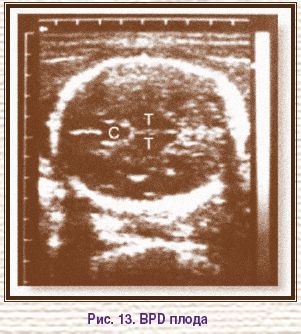

В начале 60-х годов при проведении акушерского УЗИ (Европа, США, Япония, Китай, Австралия) использовался А-режим, с помощью которого определяли признаки беременности (измеряли сердцебиение плода), локализацию плаценты, выполняли цефалометрию. В 1961 г. I. Donald (Великобритания) предложил измерять бипариетальный диаметр (biparietal diameter, BРD) головки плода (рис. 13). В этом же году он описал случай гидроцефалии у плода.